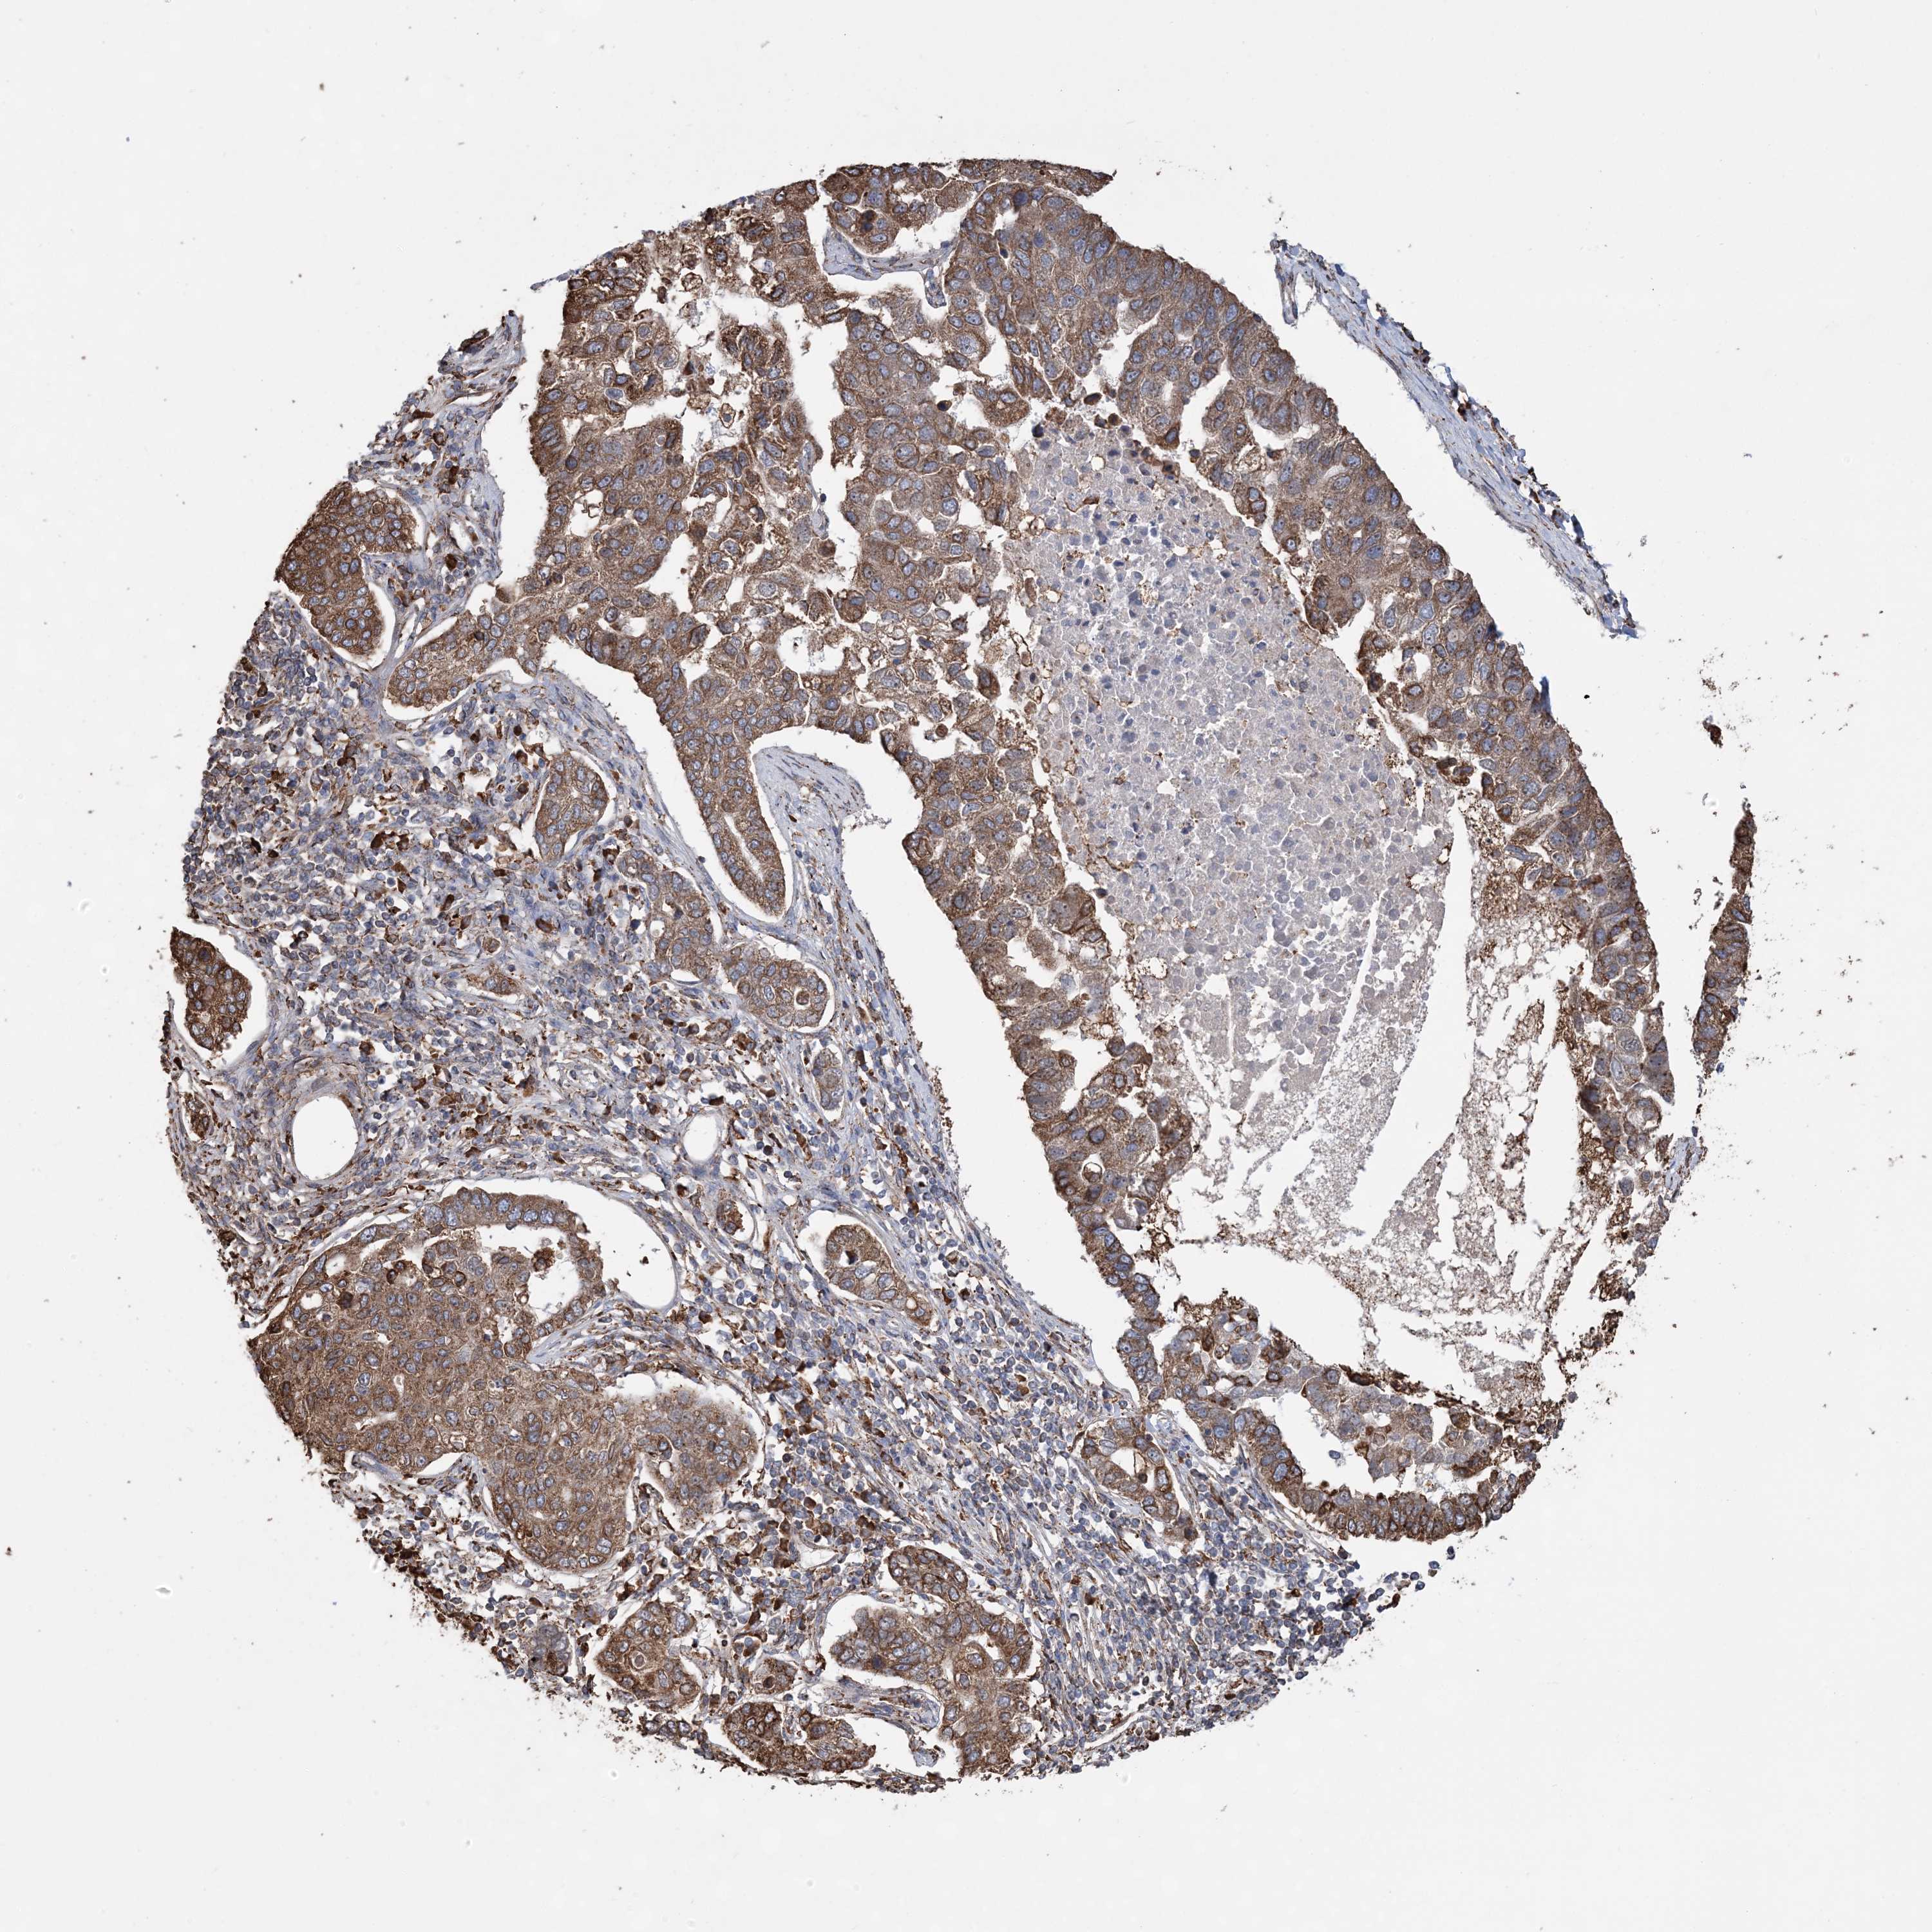

PANCREATIC CANCER - Protein expressioni

A mouse-over function shows sample information and annotation data. Click on an image to view it in a full screen mode. Samples can be filtered based on level of antibody staining by selecting one or several of the following categories: high, medium, low and not detected. The assay and annotation is described here.

Note that samples used for immunohistochemistry by the Human Protein Atlas do not correspond to samples in the TCGA dataset.

Antibody stainingi

Antibody staining in the annotated cell types in the current human tissue is reported as not detected, low, medium, or high, based on conventional immunohistochemistry profiling in selected tissues. This score is based on the combination of the staining intensity and fraction of stained cells.

Each image is clickable and will lead to virtual microscopy that enables deeper exploration of all samples and also displays staining intensity scores, fraction scores and subcellular localization as well as patient and tissue information for each sample.

Antibody HPA036389

Staining

High

Medium

Low

Not detected

Intensity

Strong

Moderate

Weak

Negative

Quantity

>75%

75%-25%

<25%

None

Location

Nuclear

Cytoplasmic/membranous

Cytoplasmic/membranous,nuclear

Adenocarcinoma, NOS